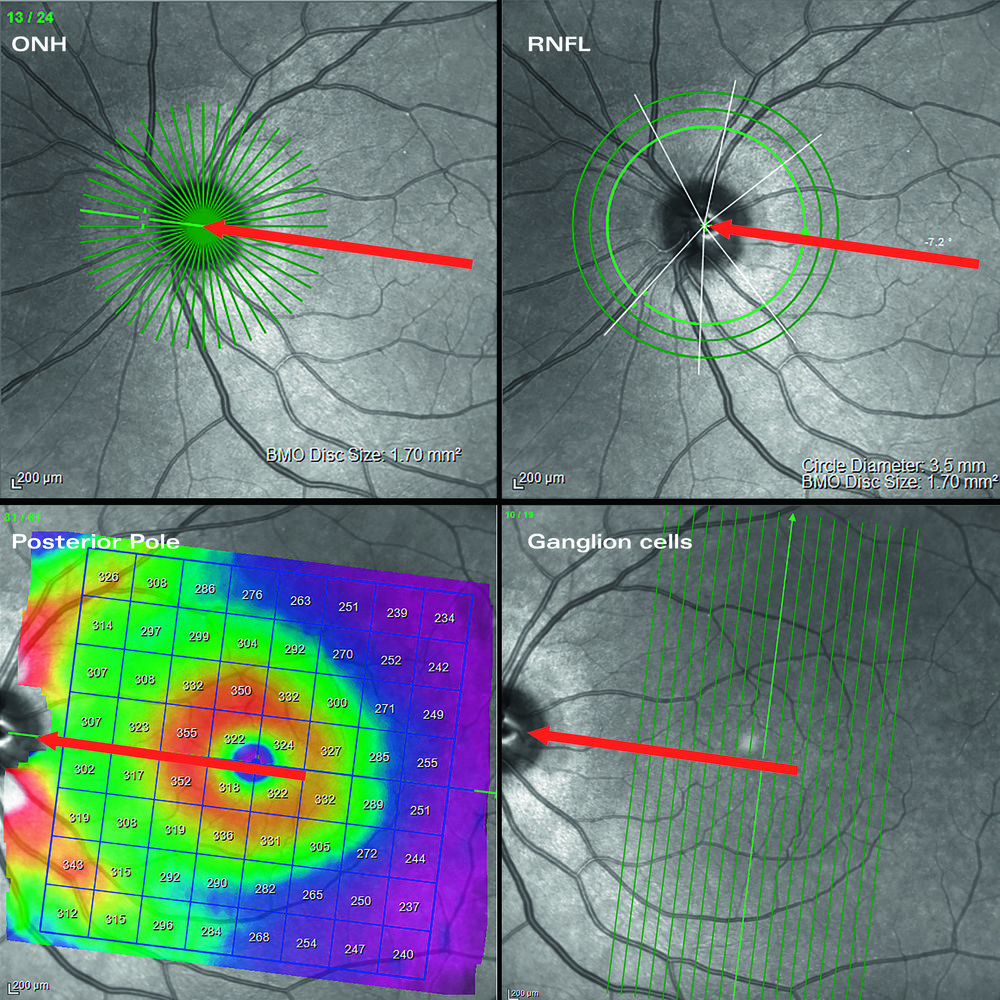

Glaucoma Module Premium Edition per Heidelberg Spectralis OCT è l’evoluzione diagnostica nel campo del glaucoma. Si tratta di un modulo opzionale applicabile su tutti i sistemi OCT basato su un concetto innovativo che rende tutte le misurazioni e la loro correlazione con database normativo oggettive e assolutamente più precise. Il modulo GMPE è dotato del sistema APS (Anatomic Positionig System), evoluzione del brevettato LiveEyeTracking (TrueTrack) di Heidelberg consente al sistema di individuare automaticamente la fovea ed il centro del nervo ottico così da allineare ogni esame alla specifica anatomia del paziente eliminando perciò tutti gli artefatti derivanti dalla correlazione con database in caso di tilting. Con la semplice esecuzione di due esami combinati il software permette di analizzare i fasci della neurorima (MRW-BMO MinimumRimWith-BruchMembrainOpening), le fibre peripapillari a tre distanze (RNFL con circle scan dedicata a tre diametri: 3,5mm-4,1mm-4,7mm) e tutto il polo posteriore sia in struttura che in asimmetria di spessore a tutti i livelli di stratificazione retinica (segmentazione a 10 strati retinici per topografia di spessore e valutazione anche del singolo strato GCL). Glacoma Module Premium Edition è anche il più valido aiuto per seguire il paziente nel tempo, sempre basato sul DNA Spectralis garantisce un riesame con mergine di errore di 1micron e genera automaticamente un grafico di progressione per ogni modalità di rielaborazione disponibile ad ulteriore completamento di un pacchetto diagnostico Premium che aggiunge un ulteriore tassello al imaging multimodale di Spectralis.